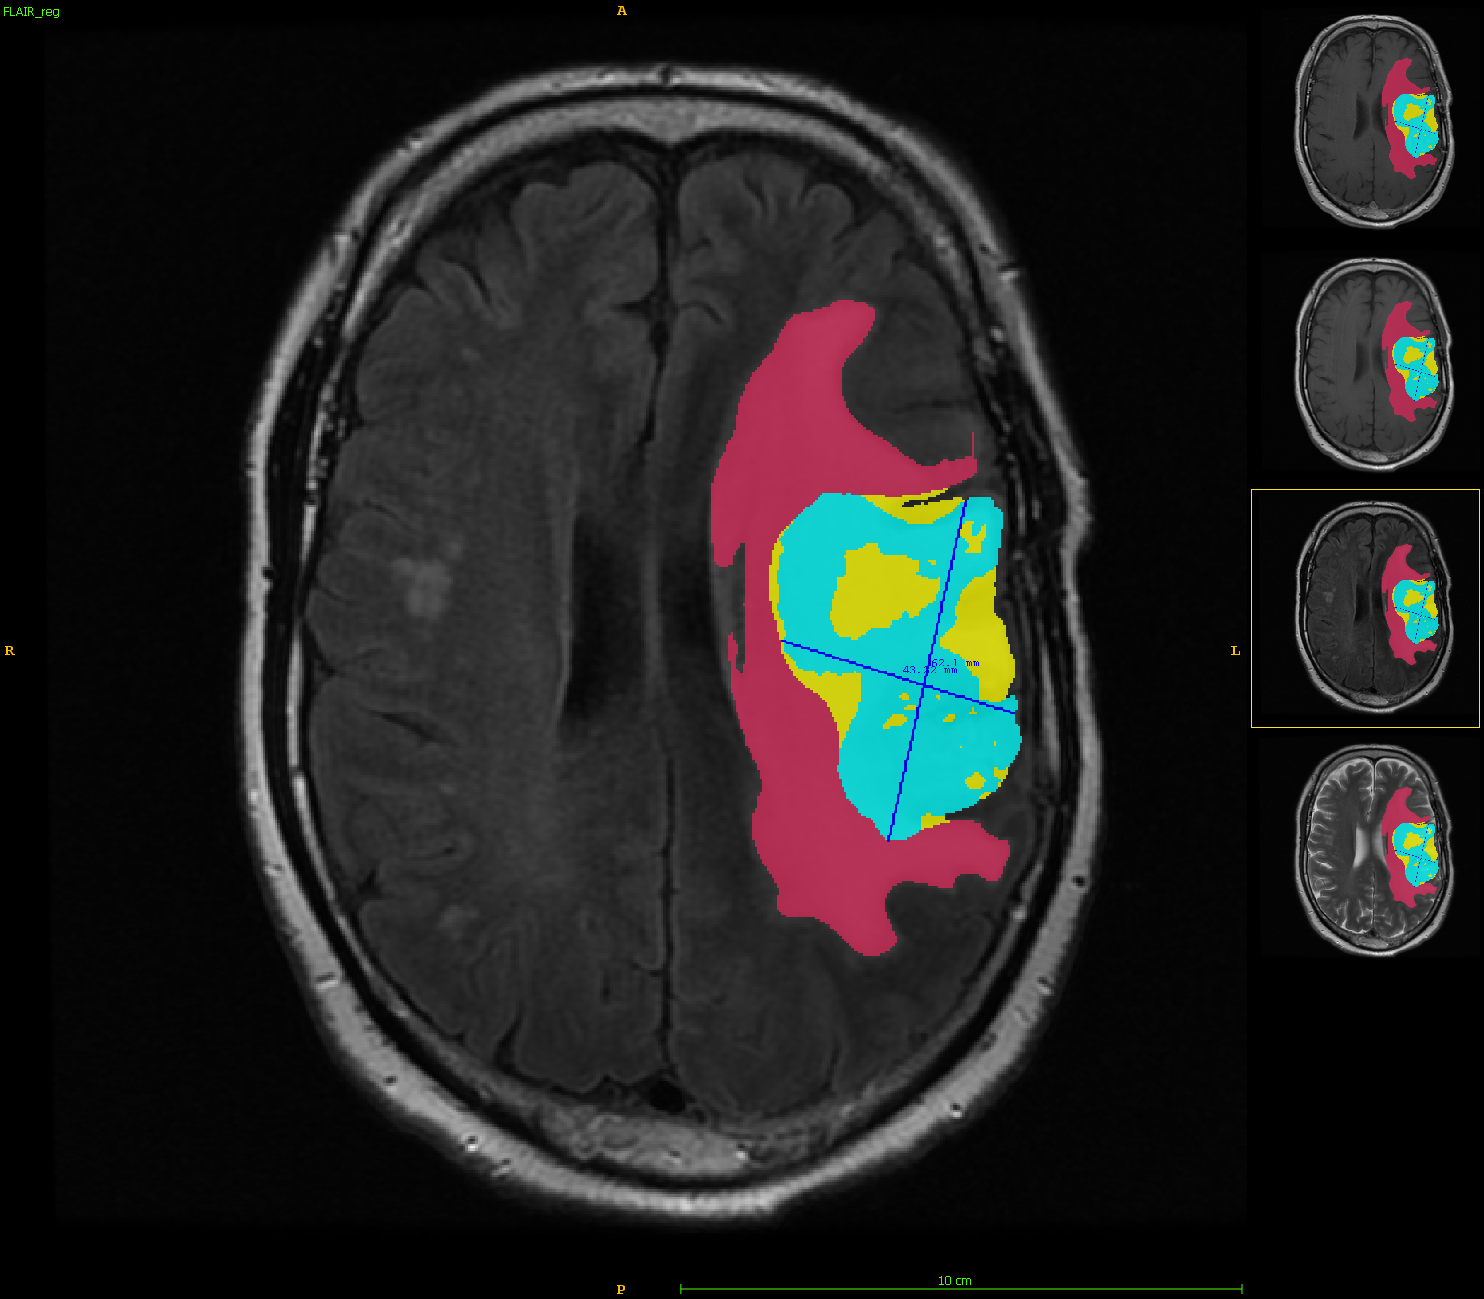

The example above, showing the before and after images, demonstrates our models’ ability to automatically segment brain tumors and identify 3 tumor subregions (edema, enhancing tumor, and necrosis). Additionally, the models provide volume and RANO (Response assessment in neuro-oncology) measurements, making them a valuable tool for monitoring patients in clinical studies.

The high performance of our algorithms is well presented in the above paper. Quantitative, qualitative, and statistical analysis revealed that our pipeline performs accurate segmentation of pre and post-operative MRIs in a fraction of the manual delineation time (up to 20 times faster than humans). Additionally, we showed that RANO measurements are not always sufficient to quantify tumor burden and developed a new method of calculating RANO that is more resistant to poor automated segmentations and jagged contouring.